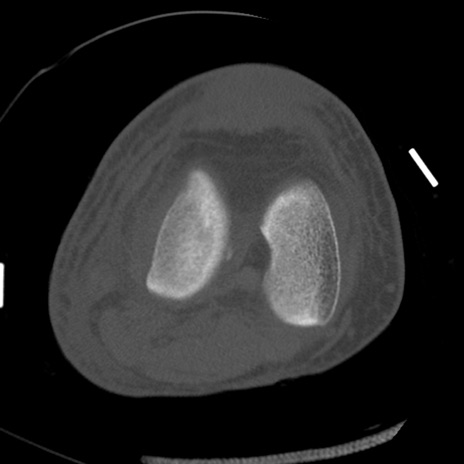

症例28 右膝関節CT(横断像)

右膝関節CT